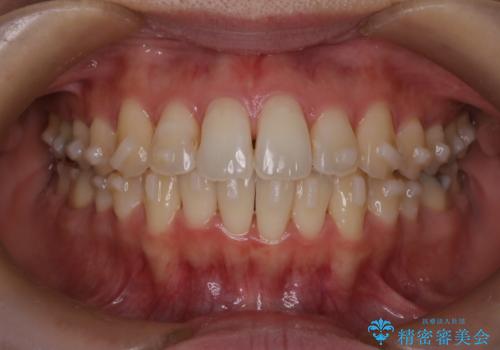

- 前歯のガタガタを主訴に来院された患者様です。

前歯の傾きも少し内側に入るように計画をたて、インビザラインにて治療を行いました。

このぐらいのガタガタであれば、インビザラインで簡単に治すことができます。